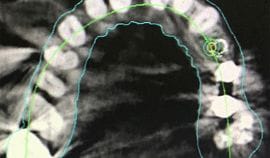

Guided implant surgery is a breakthrough technology which offers benefits previously unknown in implant dentistry. Guided implant surgery is a procedure in which precision surgical instrumentation is used in conjunction with three-dimensional CT images. Dedicated computer software, which allows visualization and manipulation of the images of the patient’s jaw bone and surrounding tissue, makes it possible for the most accurate approach to implant surgery. Traditional surgical guides are difficult to use predictably when there are no apparent anatomic references.

- Preserves vital anatomic structures since we can plan the restoration procedure around natural bone anatomy

At Terrace Oaks Dental, we used Vatech Green CT in conjunction with our digital impression to create a perfect plan for our implant surgery cases.